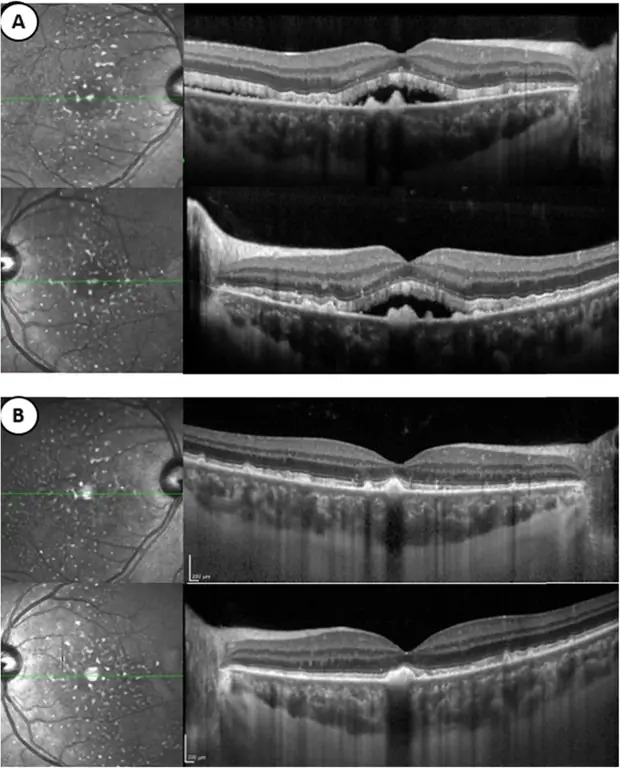

Инфракрасное отражение изображения и SD-OCT горизонтальное сканирование проходят через ямку правого и левого глаза. а При первом посещении можно наблюдать присутствие субретинальной жидкости, связанной с гиперрефлексивными отложениями перед пигментным эпителием. Есть также pachychoroid, связанный с расширением choriocapillaris. b После восьми циклов химиотерапии (9 месяцев после первого посещения) пациент находится в состоянии ремиссии. Субретинальная жидкость исчезла. Однако субретинальные отложения все еще присутствуют и толщина хориоидеи не изменяется

SD-OCT (Spectralis® OCT, Heidelberg Engineering, Dossenheim, Germany) выявил двусторонние серозные отслойки сетчатки (SRD), в которых структуры наружного сегмента выглядят удлиненными и неоднородными с наличием субретинальных гиперрефлексивных отложений. Кроме того, толщина хориоидеи была увеличена (432 мкм) при увеличенном хориокапилляре (52 мкм) (рис. 4).

При последующих посещениях BCVA улучшилось до 20/25 для обоих глаз. После начального развития хориоретинальных повреждений гипераутофлуоресцентные пятна остаются стабильными (рис. 3). Отслойки сетчатки разрешились на обоих глазах с сохранением гиперрефлексивных отложений сетчатки на SD-OCT. Толщина хориоидеи (429 мкм) оставалась неизменной на EDI, как и расширение хориокапилляра.